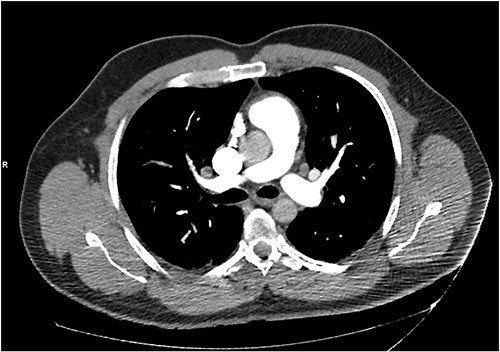

The patient was treated with IV piperacillin-tazobactam. However, he continued to have febrile temperature spikes. No growth was initially detected on blood cultures. The patient developed shortness of breath and respiratory alkalosis, for which a CT pulmonary angiography was done to exclude pulmonary embolism. Only dependent bilateral changes in the lower lobes and signs of mild pulmonary venous congestion were reported (Fig. 3). He was started on hydrocortisone, ethambutol, pyridoxine and rifampicin as empirical treatment for BCGosis. Hydrocortisone was eventually tailored down to prednisolone. Virology tests including hepatitis and immunodeficiency virus were run and these were negative. He continued spiking high temperatures and a repeat CT abdomen with IV contrast was performed which was largely unchanged from the previous scan (Fig. 4). An echocardiogram ruled out infective endocarditis. Incidentally he was in contact with a COVID-19 positive patient and was placed under quarantine for 14 days. Fortunately, he never developed COVID-19 infection. Another CT pulmonary angiography was performed in view of persisting shortness of breath but only mosaic attenuation in the lungs was present.

A repeat CT abdomen with IV contrast was performed which was largely unchanged from the previous scan, save for mild pericholecystic fluid.